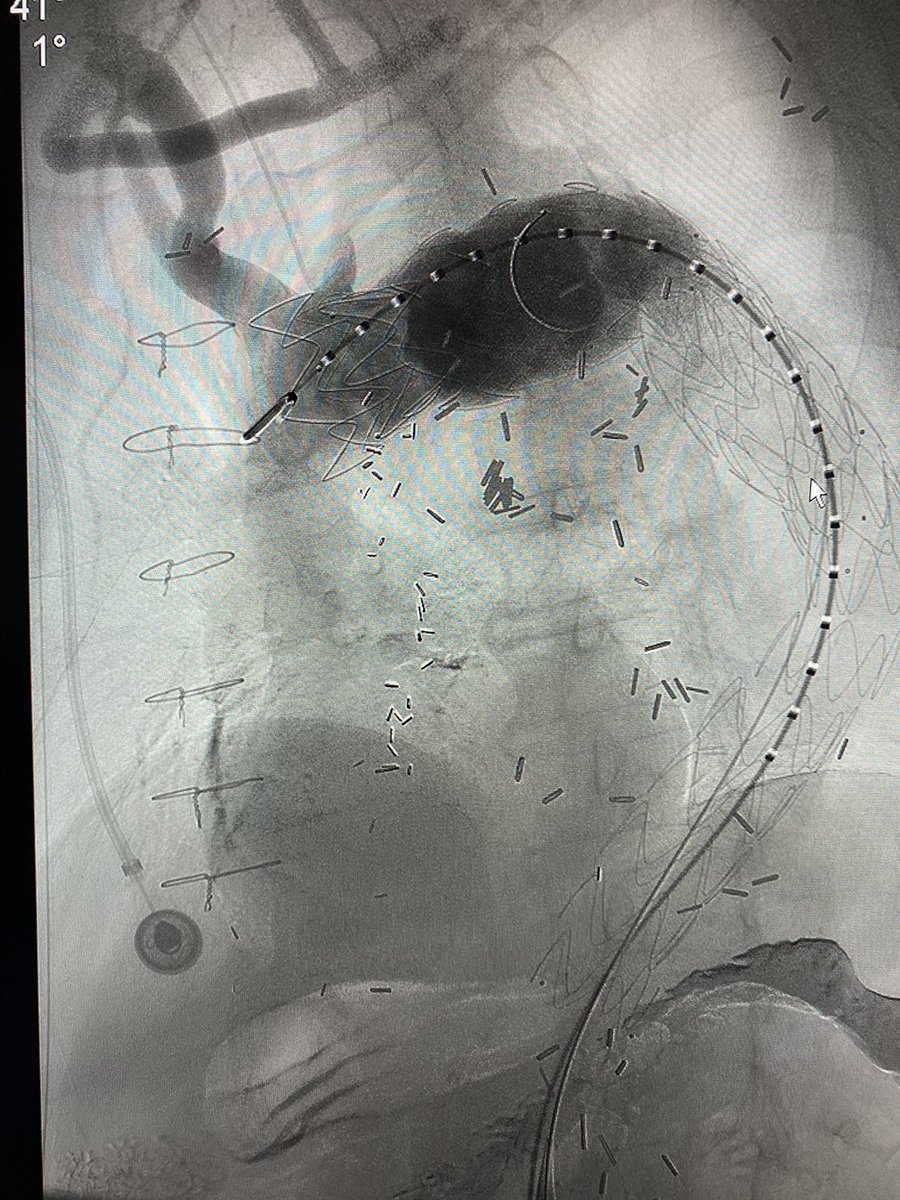

Carotid-carotid carotid-subclavian w/ #endovascular #aneurysm repair for proximal and distal anastomotic aneurysm